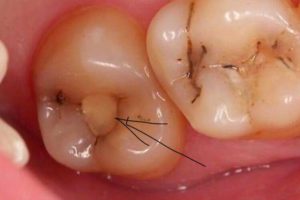

Темна полоса навколо пломби – це норма чи проблема?

Якщо на межі між пломбувальним матеріалом і емаллю зуба є темна лінія і почорнів зуб під пломбою це може свідчити про розвиток вторинного карієсу у зубі або дефект самої пломби. Вторинний карієс – це подальше руйнування запломбованого зуба під пломбою, якщо він потемнів.

Більшість людей вважає, що якщо пломба «стоїть і не випала» значить все гаразд і зуб полікований. Але темна полоса по краю реставрації якраз може бути ознакою руйнування зуба. Так, пломба стоїть, але навколо неї емаль зуба може руйнуватись і відбувається розвитоквторинного карієсу. Такі ситуації є небезпечними, оскільки пацієнта нічого не турбує, нічого не болить і він впевнений що зуб запломбований. Проте «запломбований» не означає «полікований» і здоровий. І навіть під пломбою зуб може роками темніти і руйнуватись, поки інфекція не дійде до нерва (пульпи) і він не почне боліти.